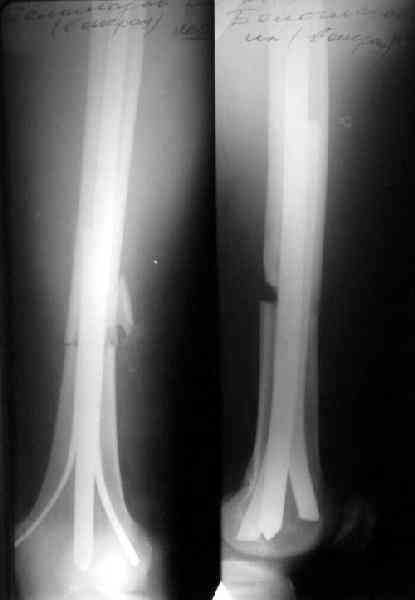

Винты удаляются через проколы (один на 2-3 винта), а пластинка через разрез 3-4 см у ее конца. Для винтов удобнее не отвертка, а инструмент для скругленного шестигранника (мы брали в "Деосте"). Пример в приложении. Понятно, что это довольно условно "закрытое" удаление. Сейчас зачастую убираем винты, штифтуем, потом выдергиваем пластинку.

Еще вариант - ввести традиционный 4-гранный, кюнчеровский, или какой есть гвоздь помощнее (можно и антеградно, но хоть даже и открыто ретроградно, традиционно со стороны перелома), а со стороны надмыщелков заклинить его одним или двумя плоскими стержнями. Пример в приложении.